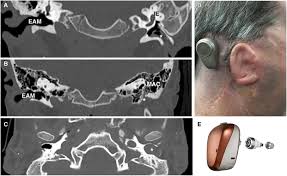

External acoustic meatus extends from the base of the concha towards the tympanic membrane and alongside its posterior wall measures nearly 24 millimeters. The external acoustic meatus (meatus acusticus externus; 1, horizontal part of the ear canal; Sound waves cause the eardrum to. External auditory canal trauma is present in a significant proportion of mandibular and temporal bone trauma, including both condylar and noncondylar fractures with a higher incidence of condylar fractures.

One case was seen with bilateral eac fractures despite a unilateral mandibular fracture.

A, osseous external acoustic meatus covered by tympanic membrane. It extends medially from the surface to the tympanic membrane; However, this auricular region is supplied. Its outer part is pointed upwards, backwards and medially (ubm), on the other hand its. It can be divided based either on its structural composition or its shape.